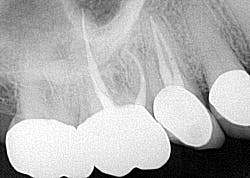

Testing of the upper right side was, for the most part, inconclusive, aside from some 6 mm pockets in the upper right quadrant. Radiograph was WNL (figure 11). A potential sinus infection was discussed, along with the possibility of a periodontal abscess. The patient was placed on antibiotics, referred to an ENT, and had scaling and root planing done on the upper right quadrant.

The report from the ENT was negative. The symptoms persisted and, in fact, started to worsen. The likelihood of a vertical root fracture was then discussed with the patient. He was referred to an endodontist who took a CBCT scan.

Evaluation by the endodontist showed a very small direct, vertical 9 mm drop on the lingual with radiolucency on the lingual root in the scan about halfway down (figure 12). Given the history of the double root canal, symptoms, and radiographic evidence, it was concluded that the patient had sustained a vertical root fracture on the lingual root of tooth No. 4. Prognosis was poor, and the tooth was removed with discussion regarding replacement options.

This case is a classic example of how elusive diagnosing these types of teeth can be and how critical a comprehensive assessment is to produce the most accurate diagnosis.